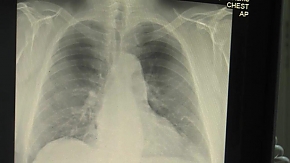

A százhalombattai önkormányzat évtizedek óta szervez tüdőszűrést a lakcímkártyával rendelkezők részére a lakosság egészségmegőrzése érdekében. A tüdőszűrés alkalmas a TBC, illetve sok más tüdőbetegség időben történő felismerésére. A TBC és a tüdőrák kezdeti stádiumában tünetmentes, ezért különösen fontos, hogy akkor is rendszeresen vegyünk részt szűrővizsgálatokon, ha semmiféle panaszunk nincs – olvasható Vezér Mihály polgármester közleményében.